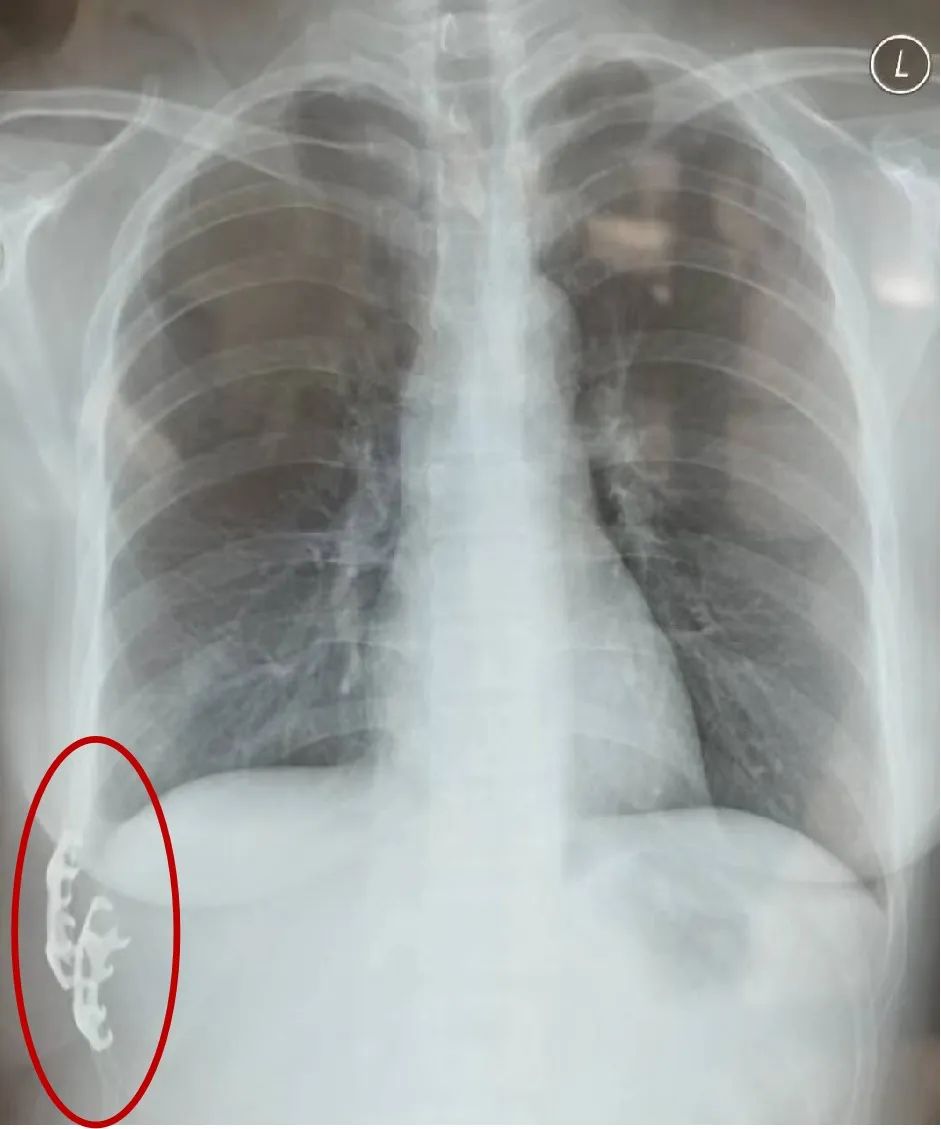

术后复查X光片,红圈中为“爪”形内固定器。丨作者供图后半辈子都可以依靠的战友工作也回归正轨,生活一地鸡毛,我俩还要一起去捡。

近年来,新型肋骨内固定材料不断出现,包括解剖钢板、爪形钢板等。一种优秀的内固定材料需要具备良好的组织相容性,无排斥反应;可塑性,能根据肋骨的解剖形状进行塑造;以及足够的强度和生物力学弹性,能够同时满足胸腔本身的弹性和顺应性以及辐射穿透的要求。目前可用于内固定的材料多种多样,临床上需要根据骨折部位、骨折严重程度、手术操作难度等情况,选择合适的内固定材料。